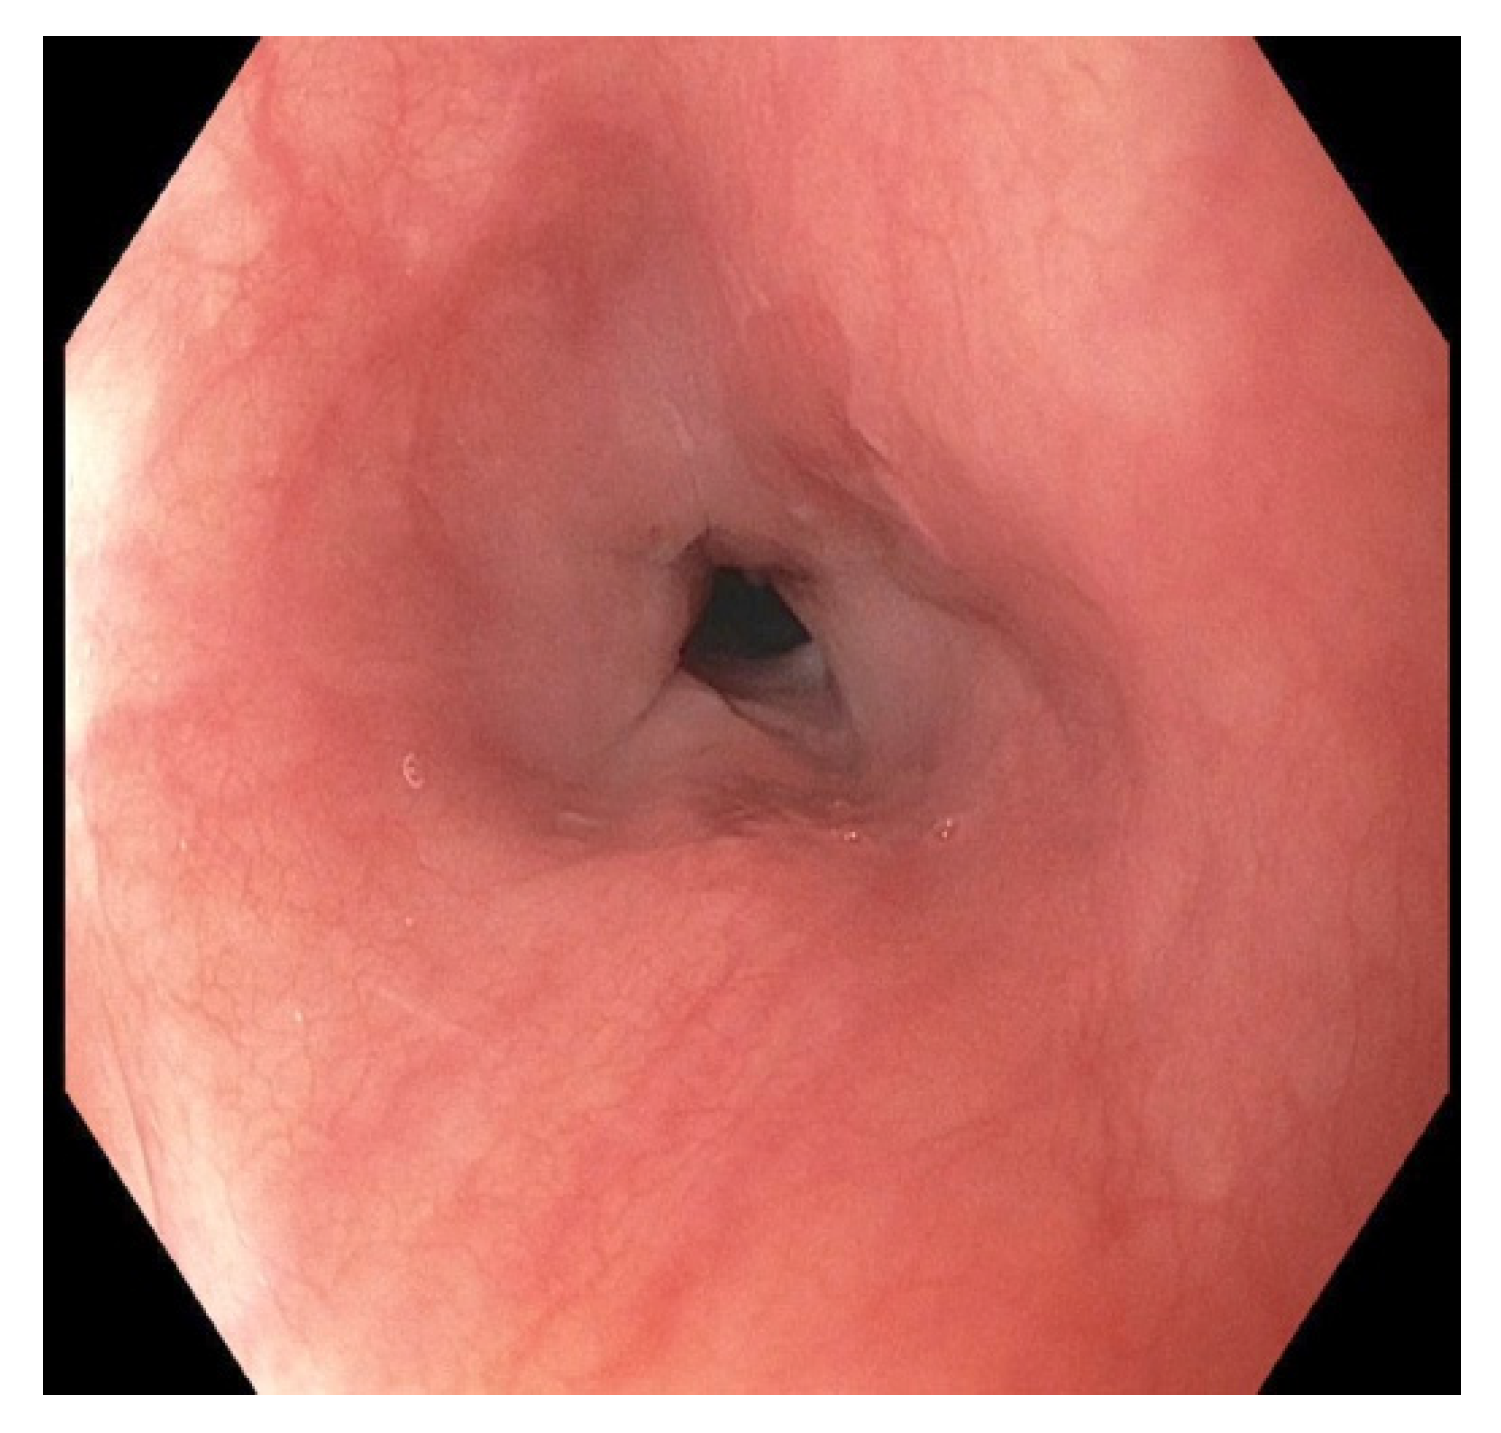

Endoscopic Evaluation for Stricture Formation Post Button Battery Ingestion

2. Case Presentation